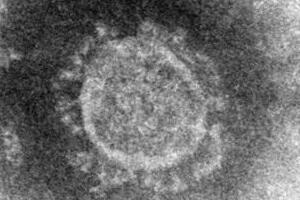

緊急事態宣言が発令され、2021年1月18日に召集される通常国会での焦点は、緊急事態宣言の根拠になっている新型コロナ特措法の改正だ。菅義偉首相は1月4日の記者会見で、改正案の意義を「給付金と罰則をセットにして、より実効的な対策を取るため」と説明しているが、野党の一部からは、「罰則」の実効性を疑問視する声もあがっている。この点をめぐる論戦が展開されそうだ。そんな中で「ロックダウン(都市封鎖)違反に対する罰則の有効性」について論じた論文が米学会誌に掲載された。ロックダウンを行ったドイツで、罰則を導入した州とそうでない州とで、感染の広がり具合を比較した論文だ。ロックダウンで罰金導入した州と、していない周辺州を比較論文は、米公衆衛生学会の米公衆衛生ジャーナル(AJPH)20年12月号に「ドイツでの新型コロナ大流行におけるロックダウン違反に対する罰則の有効性」と題して掲載された。著者は、蔚山大学医学部のパク・ヒュンジン氏と韓国陸軍士官学校のチェ・セヒュン氏。ドイツでは、南部のバイエルン州が2020年3月20日から、通勤や通院など、必要最小限の外出しか認められないロックダウン(都市封鎖)に突入。同州では、違反した人には最高で2万5000ユーロ(約318万円)の罰金刑が設けられた。周辺の州でもロックダウンが行われたが、しばらく罰金の導入は見送られ、導入が最も遅かったのがテューリンゲン州の5月12日だった。日本で検討が進んでいる改正案の罰則の対象は事業者を念頭に置いているのに対して、バイエルン州の罰則は、住民に対する外出禁止の徹底を重点においている。現地の公共放送「バイエルン放送」のウェブサイトでは、どういった場合に外出可能かの例を挙げながら、「違反すればいかなる人でも、最大2万5000ユーロの罰金を課される可能性がある」としている。学校、店舗、バーなどの閉鎖やマスク着用の義務化といったロックダウンの内容はバイエルン州とそれ以外で、ほぼ同じ条件だった。そこで、バイエルン州がロックダウンに突入する直前の3月15日から、他の州でも罰金が導入される直前の5月11日の期間について、ロベルト・コッホ研究所がまとめた感染状況データを比較した。その結果、感染者1人が何人に感染させるかを表す「実効再生産数」(1より大きいと感染が拡大し、小さいと縮小していることを示す)は、バイエルン州は他の州よりも0.32低く、新規感染者数の伸び率も、バイエルン州の方が6ポイント低かった。バイエルン州以外の州でも、ロックダウンにともなって実効再生産数は低下傾向になり、新規感染者数も減少したが、バイエルン州の方がさらに効果が出た、ということだ。ただ、高齢者については違いが認められなかったといい、「高齢者は移動しない、という特徴によるものではないか」とみている。「適切な政策の執行がなければ、法律を守っている市民だけが被害を受ける」新型コロナ特措法の改正案に盛り込まれる具体的な罰則の内容や、罰金の額はまだ固まっておらず、対象の性格の違いもあり、この論文の内容がどの程度日本に当てはめられるかは不明だ。ただ、著者の2人は日本の状況を念頭に「経済的罰則によって、コロナ禍での制限がさらに実効性を持つと確信している。多くの人々が政府の指針を軽視しており、適切な(政策の)執行がなければ、長引くコロナ禍で法律を守っている市民だけが被害を受けることになる」とするコメントをメールでJ-CASTニュースに寄せている。(J-CASTニュース編集部 工藤博司)